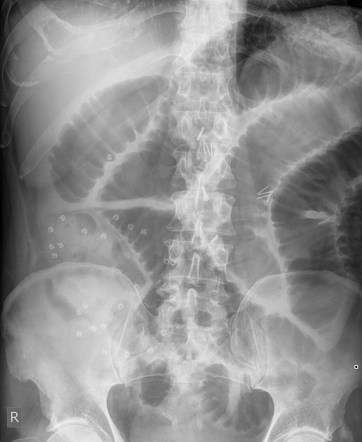

What is the 3/6/9 rule?

Diameter of intestines should be no greater than:

3cm in small bowel

6cm for colon

9cm for caecum